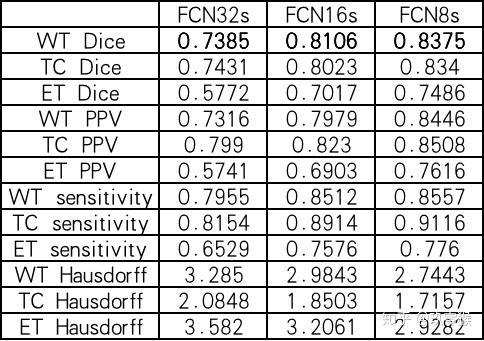

如果要训练FCN8s,则运行下面指令

此外还可以训练FCN16s、FCN32s

运行下面指令评价测试结果以及GT文件的指标,想了解更多指标的信息包括Dice、Hausdorff、IOU、PPV等,可以参考我这一篇(分割常用评价指标)

运行的结果: